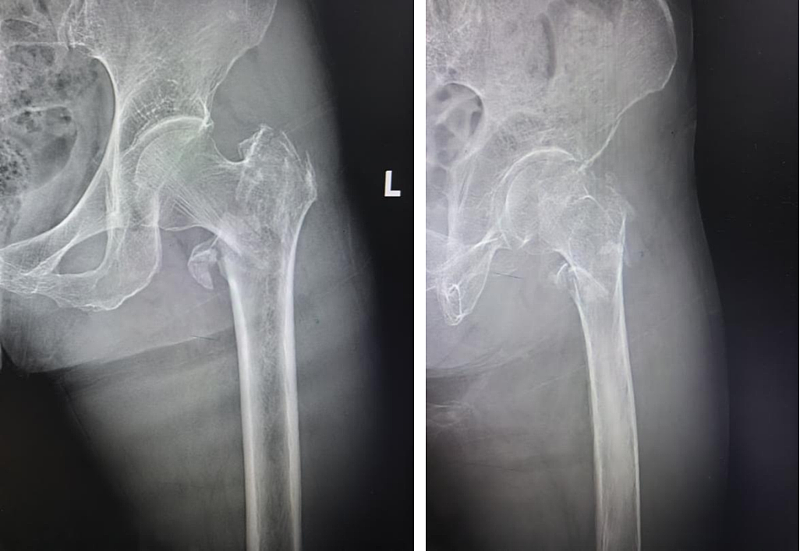

老人被紧急送医后,医院第一时间开启高龄骨折绿色通道,加急完成心脏、肺部、凝血功能等检查。然而,检查结果却远超预期——左股骨粗隆间粉碎性骨折、入院时双下肢静脉血栓形成、多种基础病交织,让治疗难度陡增。看着卧床不起、痛苦呻吟的老人,家属满心焦灼:“年纪这么大,还带着血栓,这手术还能做吗?”

危急时刻,运动医学科在北京大学第三医院驻延专家陈有荣及科室主任庞军的带领下,紧急组织病情研讨。经过反复评估、缜密论证,在充分征得家属同意后,团队最终决定为患者实施微创PFNA内固定术。同时针对老人体弱、贫血、合并血栓等问题,团队同步采取纠正贫血、抗感染、抗血栓等对症措施;麻醉科精准调控患者血压、血糖至手术安全范围。

在无影灯下,运动医学科团队凝神聚力、精细操作。2小时后,螺旋状固定钉顺利植入,也为老人后续康复打下坚实基础。目前,患者正在营养科和康复科医生的专业指导下,稳步进行恢复训练。

高龄骨折患者的救治,考验的不仅是单一科室的技术,更是医院多学科协作的综合实力。此次为患者实施的微创PFNA内固定术,相比传统开放手术,不用大范围切开骨折部位,既能减少软组织损伤、保护骨周血管,又能实现骨折端的牢固固定,帮助患者更早下床活动,降低卧床并发症风险。